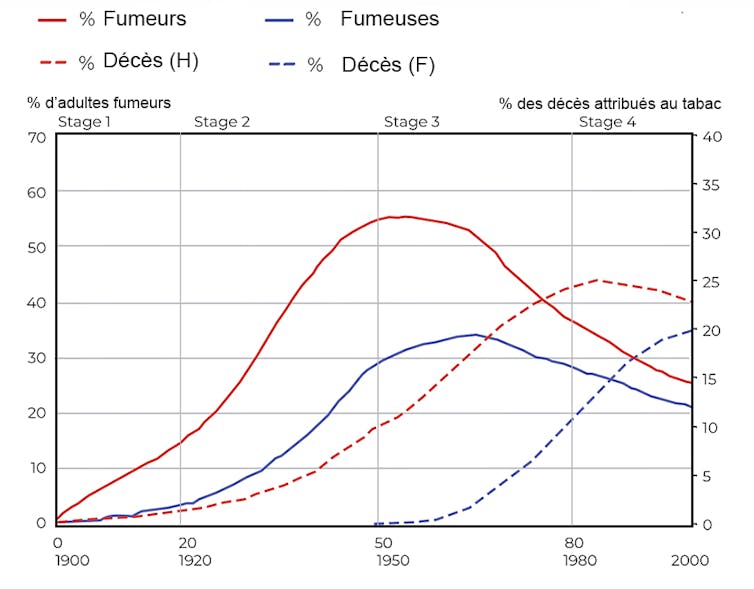

Un graphique datant de 1994, et désormais célèbre, circule chez les responsables en santé publique. Il illustre, tragiquement, la dynamique de l’épidémie des maladies causées par le tabac au fil des décennies.

La courbe montre quatre grandes étapes dans l’évolution de l’épidémie de tabagisme et des maladies associées.

Première phase (une vingtaine d’années) : le tabagisme se répand, mais les maladies qu’il entraîne sont encore négligeables.

Seconde phase (trentaine d’années) : la consommation de cigarettes atteint son pic chez les hommes et augmente chez les femmes, mais les maladies associées commencent à augmenter chez les premiers.

Troisième phase (trentaine d’années) : la consommation de cigarettes se stabilise chez les hommes avant de décroître, mais atteint seulement son pic chez les femmes. Les maladies associées augmentent toujours chez les premiers et commencent leur croissance chez les secondes.

Quatrième stade (depuis les années 1980) : le tabagisme diminue chez les deux sexes, mais les maladies se développent toujours. Ces écarts sont connus sous le nom de périodes de latence en épidémiologie.

Le mésothéliome (cancer de la plèvre, qui entoure les poumons) causé par l’inhalation de fibres d’amiante suit également ce schéma. La période de latence entre l’exposition initiale et l’apparition des symptômes peut atteindre jusqu’à 50 ans.